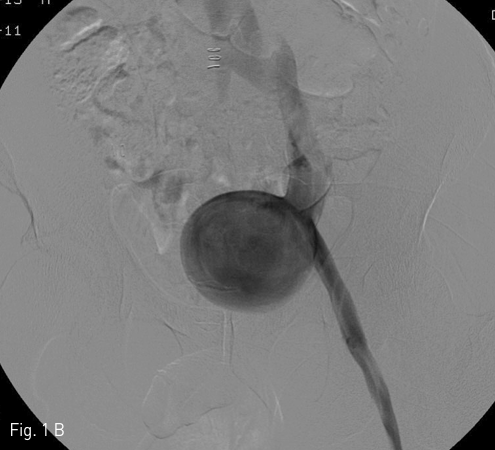

야뇨증상과 좌측 하복부 종괴에 대한 평가를 위해 시행한 CT에서 좌측 골반강에 약 5.6 X 5.2 X 7.4 cm 크기의 경계가 뚜렷하고 조영증강을 보이는 병변이 있으며, 방광의 전외측을 압박하고 있었다. 이 병변은 외장골 정맥과 연결되어 있고, 외장골 정맥과 동일한 정도의 조영증강을 보였다 (Fig. 1A). 좌측 하지에서 시행한 정맥조영술에서 좌측 외장골 정맥에서 기인하는 saccular aneurysm이 확진되었다 (Fig. 1B).

Fig 1B

(B) Venography shows contrast filling in the aneurysm originated from the left external iliac vein.